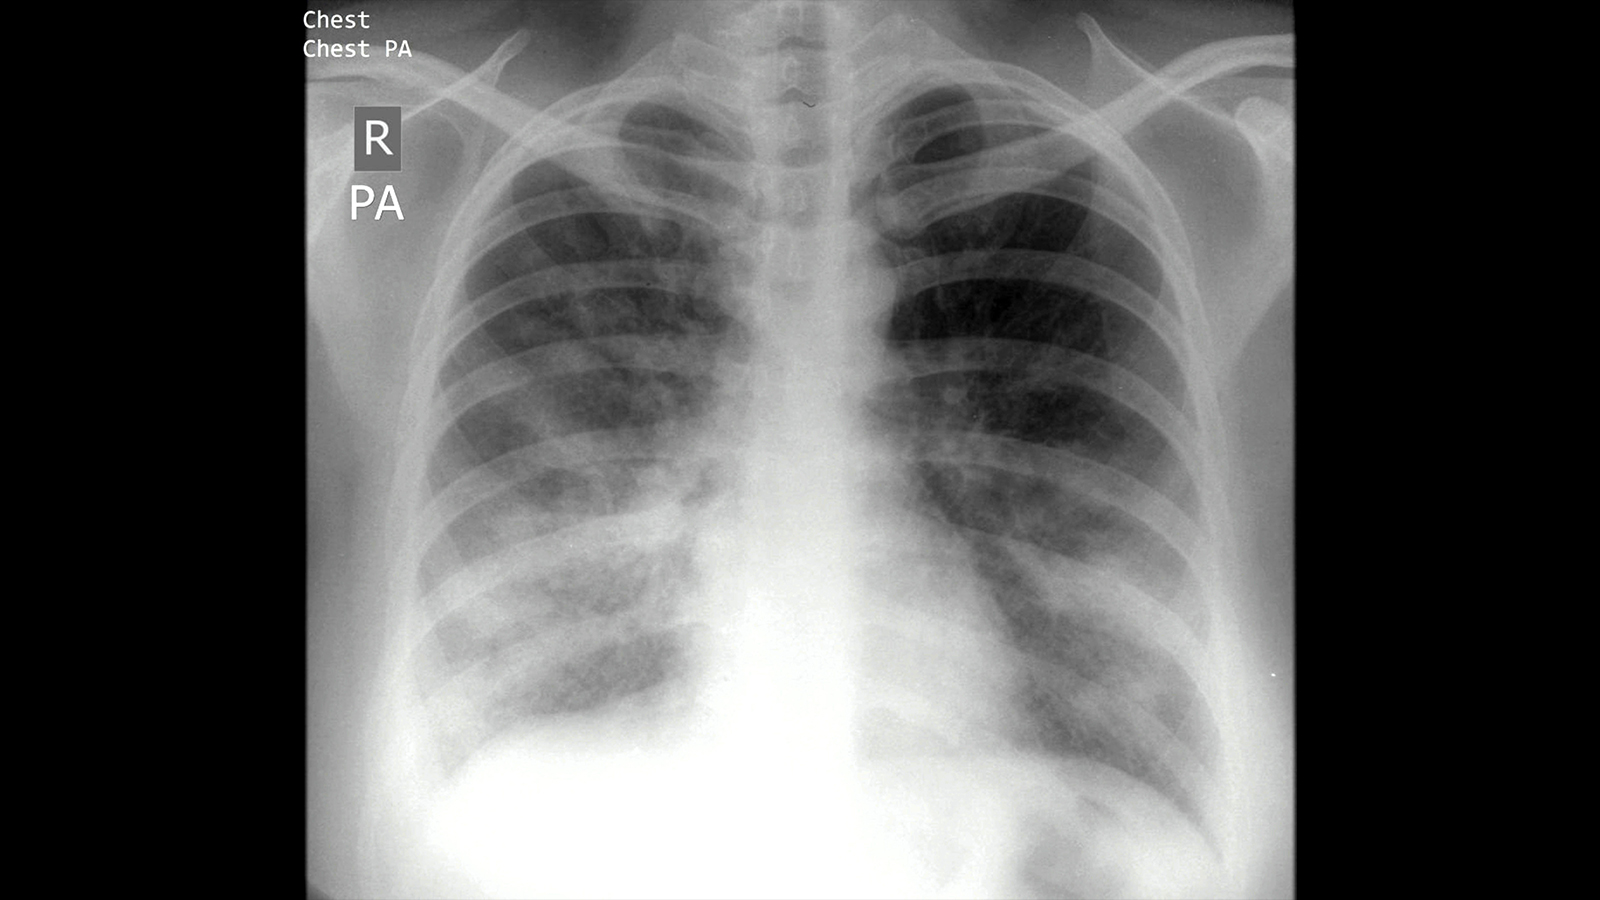

Combination Model May Improve Diagnosis of Serious Respiratory Infections

MedPage Today) — A model that combines a host biomarker with a generative artificial intelligence (AI) analysis of electronic medical records may improve the diagnosis of lower respiratory tract infections (LRTIs), such as pneumonia, in critically…